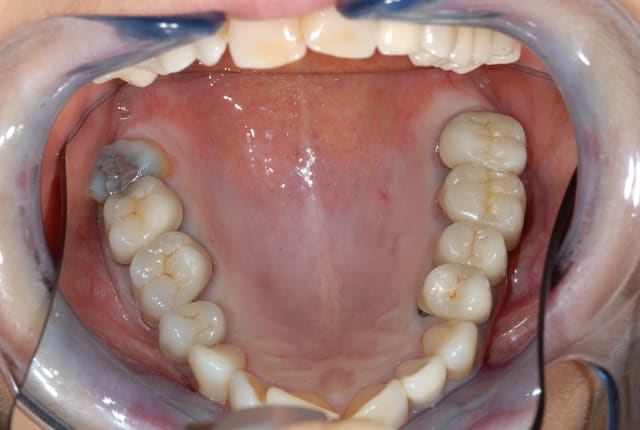

Bonjour à tous

je souhaiterai gagner de la gencive attachée en vestibulaire de 46 et 45 avant la pose des dents.

Dans le cas présenté, j avais fait extraction implantation de la 46 et pose de l implant en 45, la gencive n était pas terrible déjà, j ai gagné du conjonctif en 45 grâce à mon trace d incision mais pas en 46.

Je préfère pour cette raison, même après la pose des implants, améliorer le site et avoir un bandeau de gencive attachée avant de poser les dents.